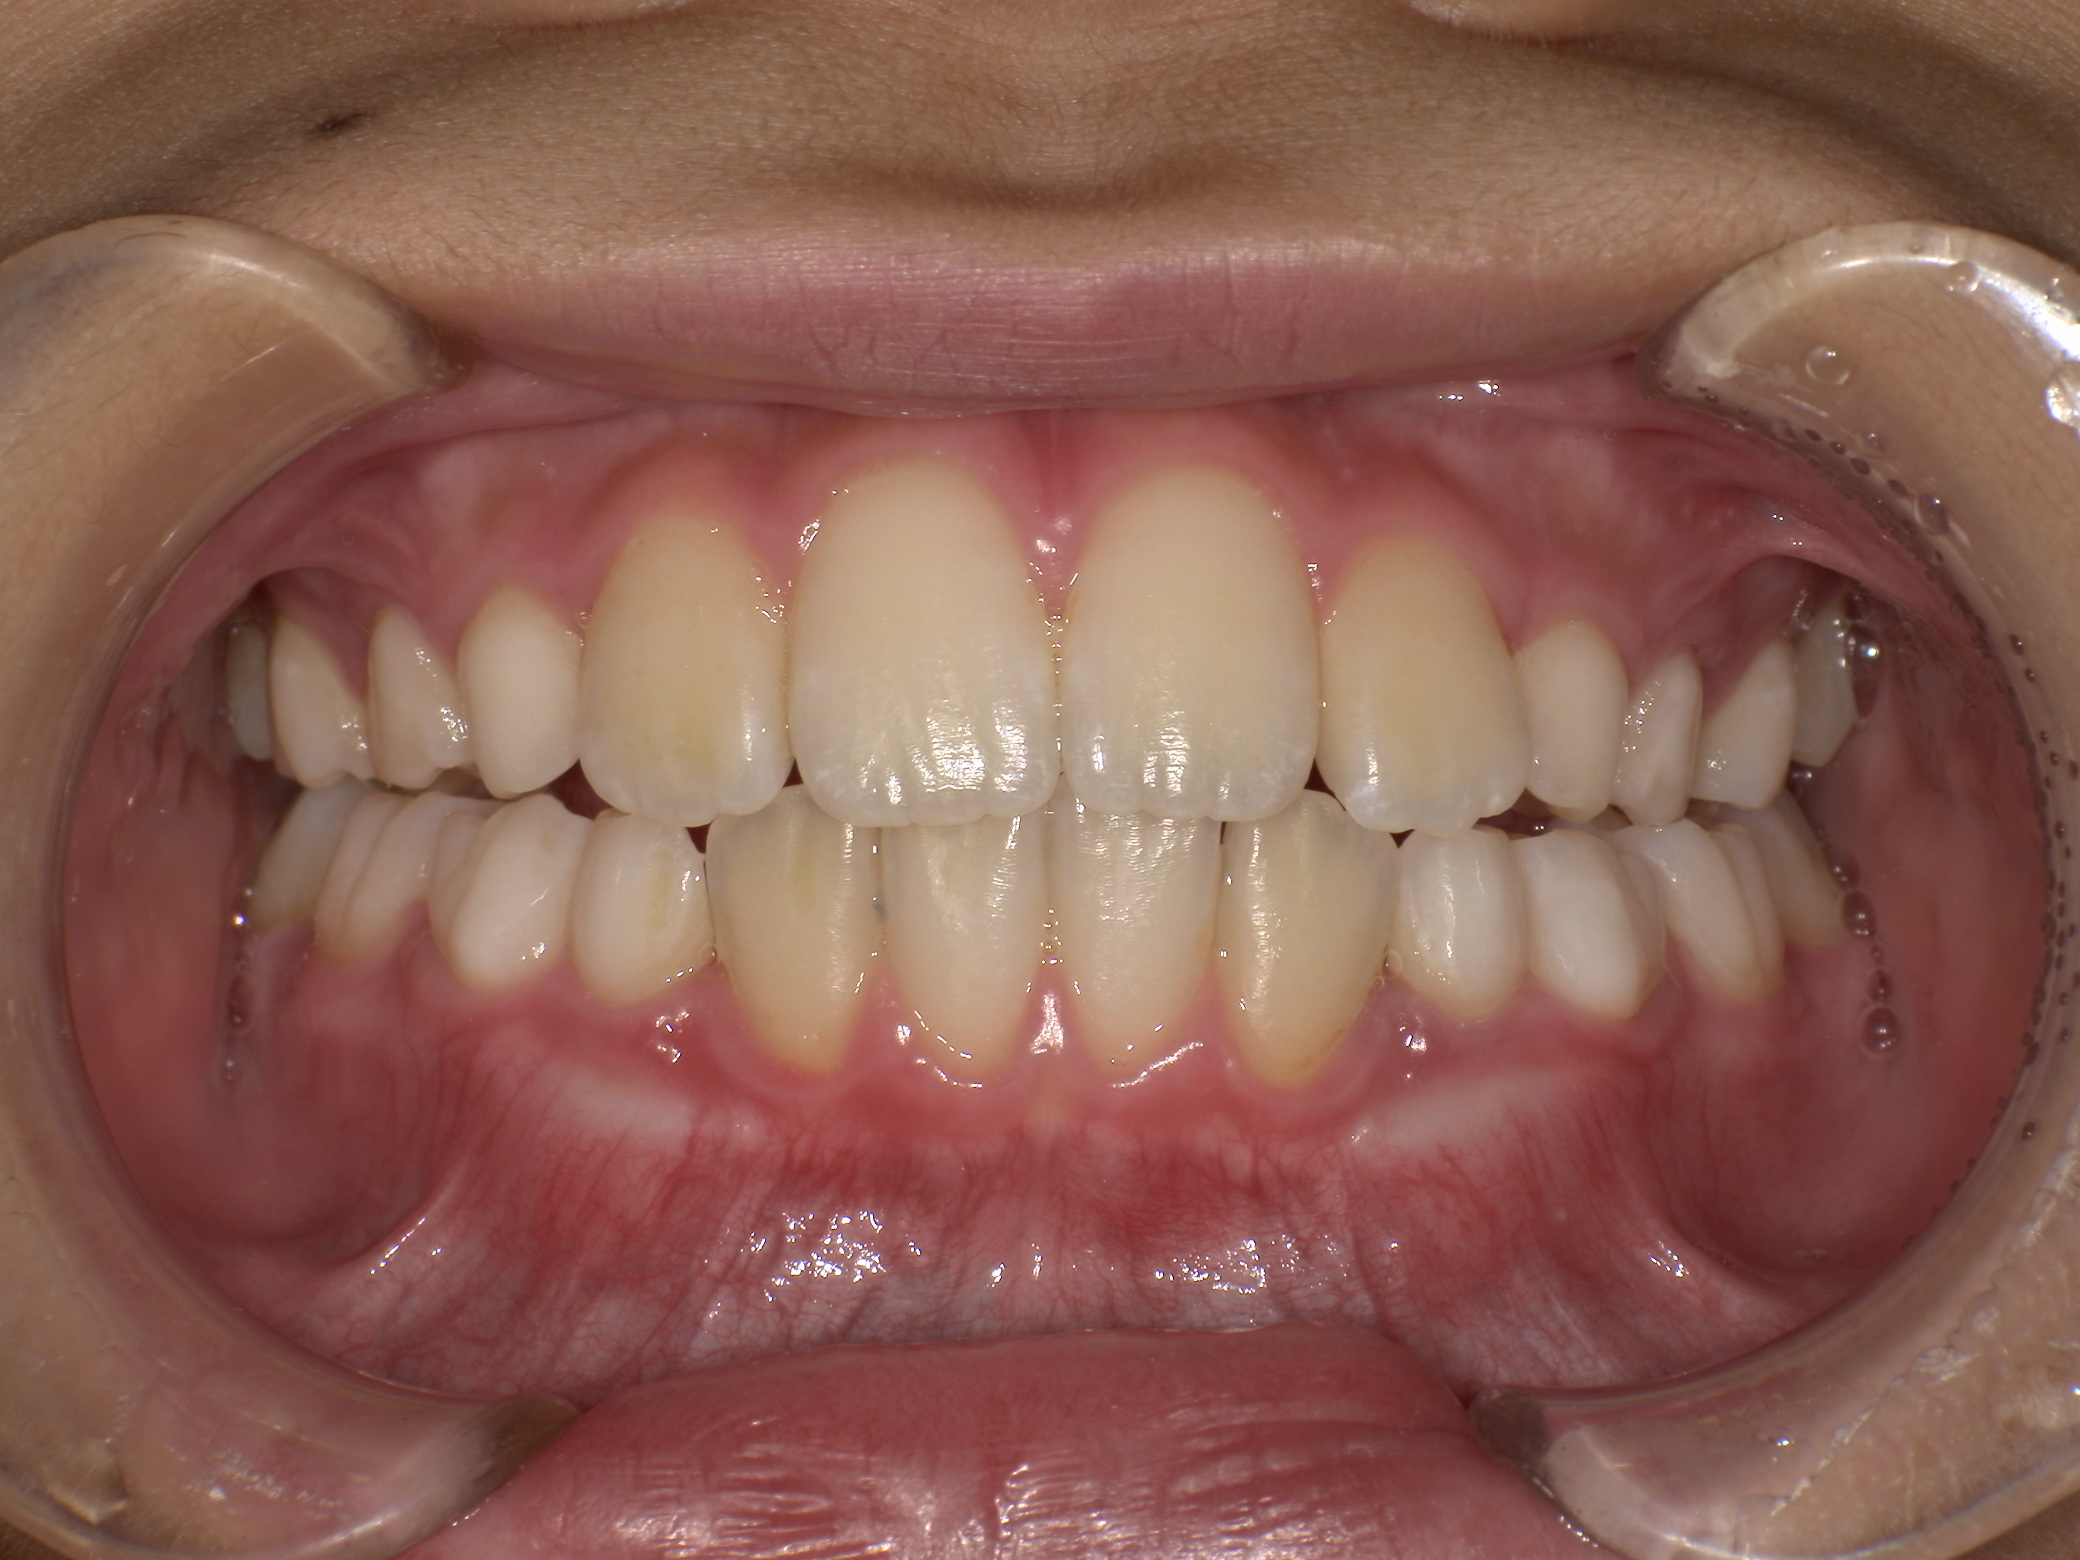

| 年齢・性別 | 8歳9ヶ月の女児 |

|---|---|

| 主訴 | 歯並びの乱れを気にされて来院された患者様です。将来的なスペース不足と歯のねじれ(翼状捻転)が懸念されました。 |

| 治療期間・回数 | 2年10ヶ月・19回 |

| 費用 | 430,000円(税別) |